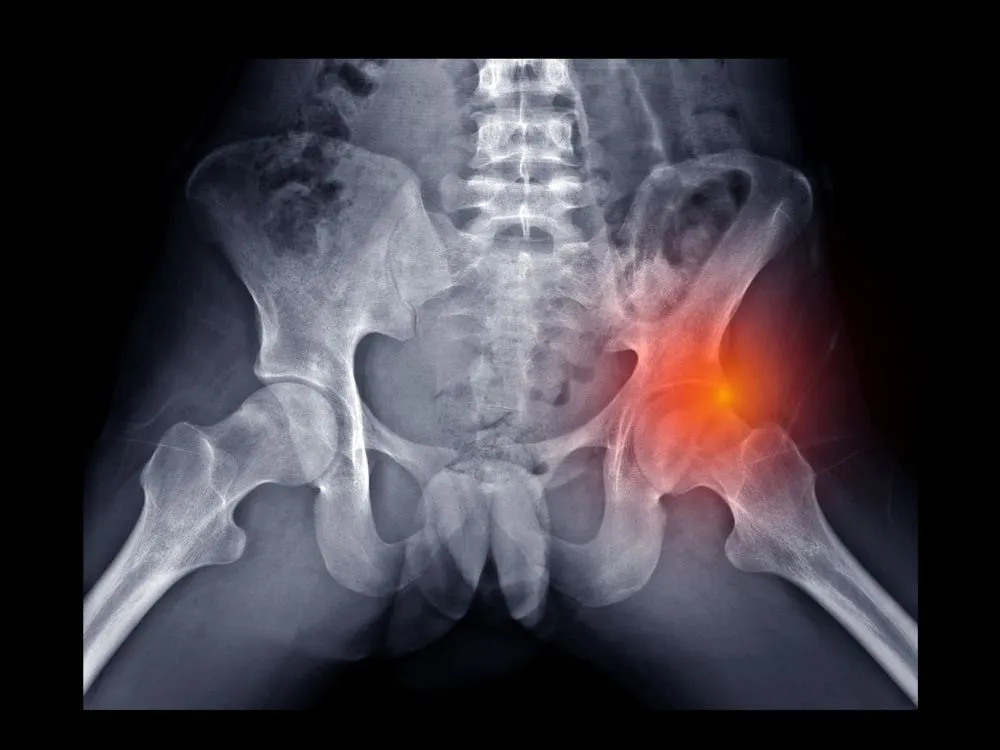

Skręcenie stawu biodrowego to poważny uraz, który może wystąpić w wyniku nagłego ruchu, upadku lub podczas aktywności sportowej. Objawy tego schorzenia są zazwyczaj bardzo wyraźne i mogą znacząco wpłynąć na codzienne życie. Najczęściej pacjenci skarżą się na ostry ból w okolicy biodra, który nasila się podczas chodzenia czy zmiany pozycji. Dodatkowo, mogą występować opuchlizna oraz ograniczenie ruchomości stawu, co utrudnia wykonywanie podstawowych czynności.

Skręcenie stawu biodrowego to uraz, który może prowadzić do różnych objawów, wpływających na codzienne życie pacjenta. Najważniejsze z nich to ostry ból, opuchlizna oraz ograniczenie ruchomości. Te objawy mogą występować zarówno podczas aktywności fizycznej, jak i w spoczynku, co znacząco utrudnia normalne funkcjonowanie.

W przypadku skręcenia stawu biodrowego, ból jest jednym z najbardziej charakterystycznych objawów. Może on być intensywny i przenikliwy, co sprawia, że pacjenci często mają trudności z poruszaniem się. Dodatkowo, opuchlizna w okolicy stawu oraz siniaki mogą być widoczne, co również wskazuje na powagę urazu. Ograniczenie ruchomości stawu, szczególnie w zakresie odwodzenia i rotacji, jest kolejnym symptomem, który może wskazywać na skręcenie.